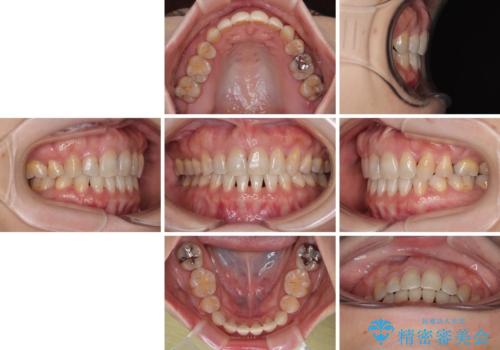

上顎骨に対して下顎骨がやや前方位に位置しているため、歯肉退縮を回避するために下顎前歯をあまり内側に移動させることができない状況でしたが、十分に口元の突出感を改善することができました。